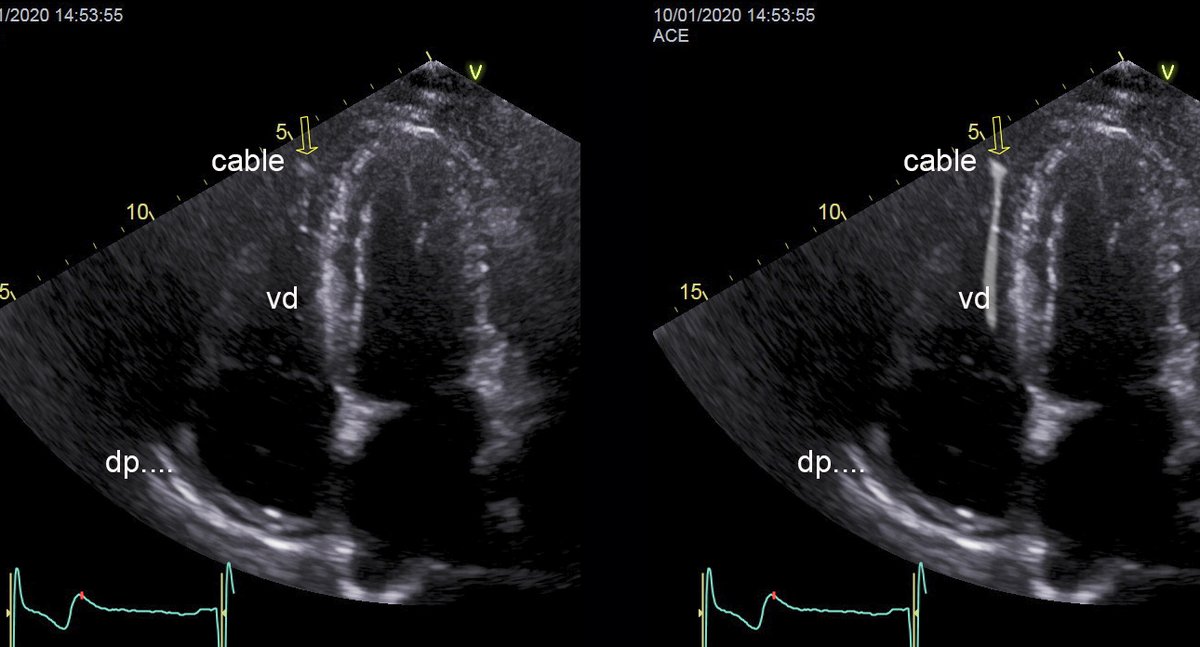

Subcostal shows a new small peric eff

Subcostal shows a new small peric eff

look the position of the cable, apical modified for rv view